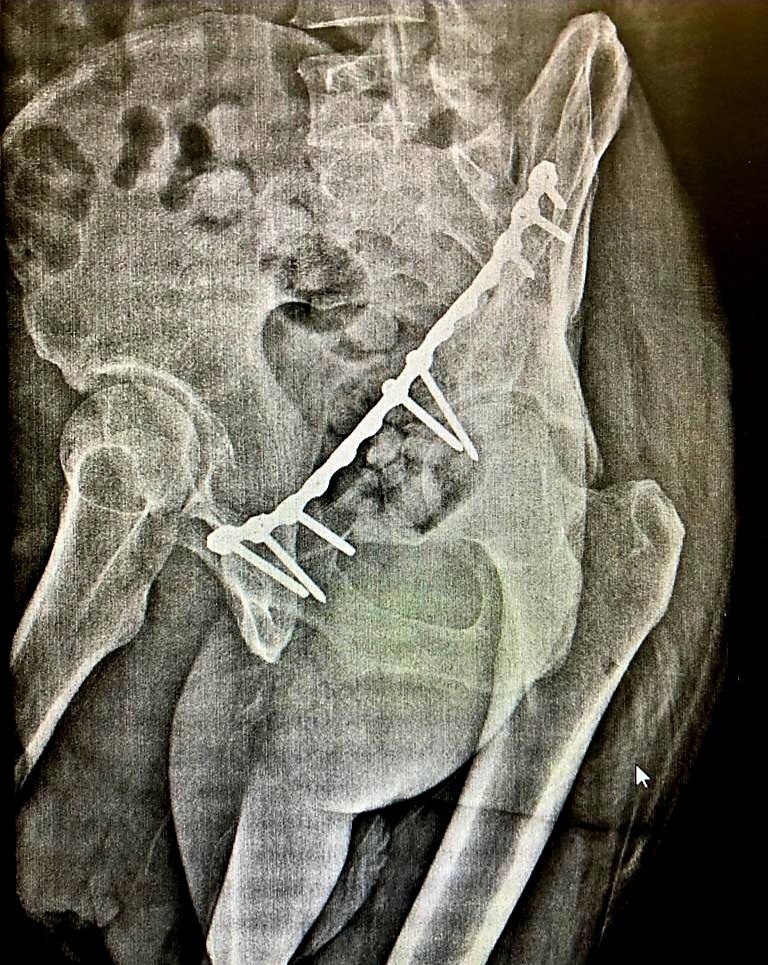

Мужчина был направлен из Домодедовской городской больницы в травматологическое отделение ГБУЗ МО «Раменская областная больница» с целью оперативного лечения вертлужного перелома костей таза со смещением бедра. В отделении травматологии пострадавшему была произведена компьютерная томография костей таза и принято решение о необходимости оперативного лечения. Хирурги-травматологи блестяще провели сложную операцию по устранению смещения бедренной кости и восстановлению вертлужной впадины, после чего пациент смог встать на костыли.

«В перспективе мы прогнозируем у пациента полное восстановление тазобедренного сустава и возможность передвижения без ограничений. Являясь травмоцентром первого уровня, мы часто принимаем пациентов из близлежащих районов с переломами костей таза, которым необходимо оперативное лечение», — рассказал заведующий травматологическим отделением ГБУЗ МО «Раменская областная больница» Всеволод Владимирович Ушанов.